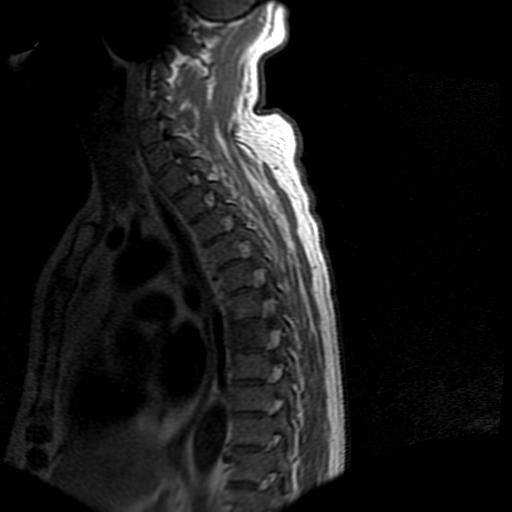

标题: MRI0985:胸椎.68岁男性,胸部疼痛,

68岁男性,胸部疼痛,不适。

t7椎体前1/3信号略减低,椎体上下面凹陷,相应脊髓几周边软组织信号未见改变。考虑:椎体退变。

胸7椎体楔状变形及信号异常,附件未见明显异常信号.椎间隙正常.未见软组织块影.考虑骨质疏松所致压缩性骨折可能大.

胸7椎体楔状变形及信号异常[t1t2 均为低信号],附件未见明显异常信号.椎间隙正常.未见软组织块影.考虑陈旧性压缩性骨折伴退变。

首先需除外单发成骨性转移瘤可能。

转移瘤也不能排除